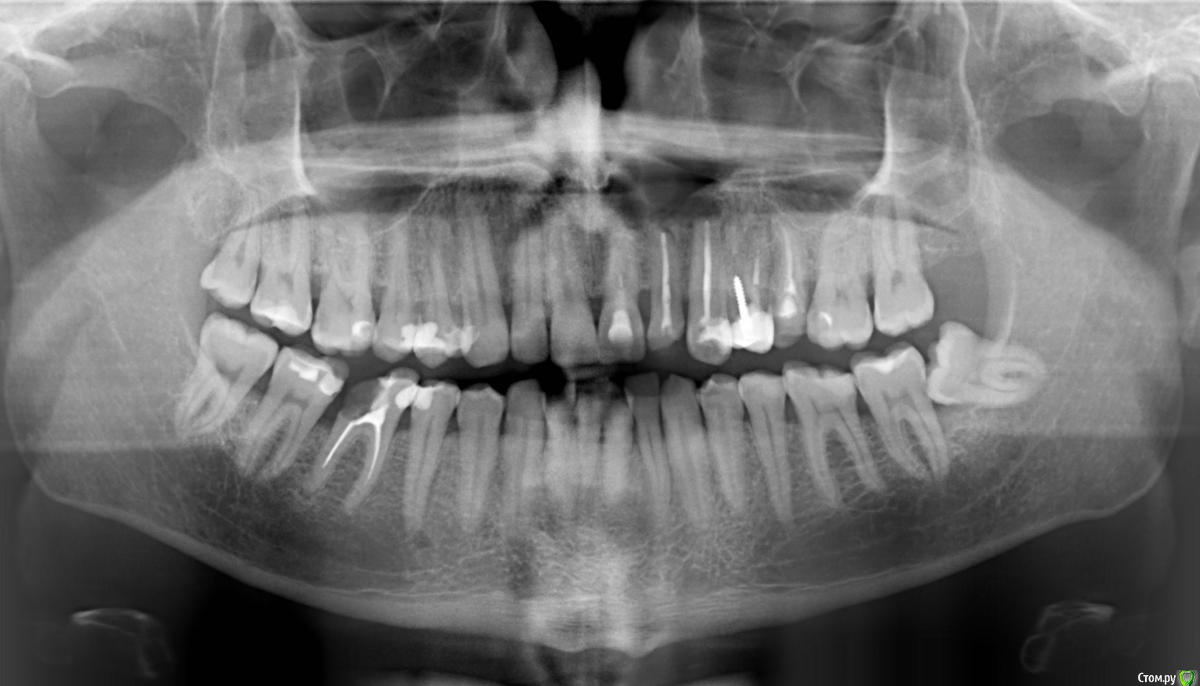

Olaf5 Опубликовано 18 сентября, 2017 Поделиться Опубликовано 18 сентября, 2017 Добрый день!Сломался зуб (шестерка, правый, нижний) с старой пломбой и тремя запломбированными каналами - отвалилась добрая половина. Ортопантомограмма показывает небольшую гранулему. Предложенный план лечения предполагает эндодонтическое лечение с микроскопом, консервативное лечение, вставку и коронку из диоксида циркония. Все вместе займет порядка 5-6 недель, потребует более 1000 евро (г.Санкт-Петербург), при этом лечение будет "качественным, но безгарантийным". Буду благодарен, если поможете найти ответы на следующие вопросы: нужна ли эндодонтия и каковы шансы с помощью консервативного лечения избавится от гранулемы; действительно ли подобные процедуры при такой цене не имеют гарантии; можно ли восстановить зуб другими способами (менее затратными или менее нервными ) ) - например создав "большую" пломбу или установив имплант? Ссылка на комментарий

St. Опубликовано 18 сентября, 2017 Поделиться Опубликовано 18 сентября, 2017 Предложенный план лечения предполагает эндодонтическое лечение с микроскопом, консервативное лечение, вставку и коронку из диоксида циркония Все корректно и рационально, если же хочется сэкономить можно рассмотреть менее эстетичную металлокерамическую коронку вместо циркониевой. нужна ли эндодонтия да каковы шансы с помощью консервативного лечения избавится от гранулемы Где-то 80% успеха в среднем действительно ли подобные процедуры при такой цене не имеют гарантии вопрос не в стоимости , а в самой процедуре. Результат зависит не только от доктора и того что он сделал, а еще и от вашего организма.На лечение каналов гарантии не существует. можно ли восстановить зуб другими способами (менее затратными или менее нервными ) ) - например создав "большую" пломбу или установив имплант? Пломбой нельзя.Удаление и имплантация - да это альтернативный вариант. З.Ы. обратите еще внимание на зуб мудрости внизу слева( его нужно планово удалять, пока еще не испортил соседний) и верхний правый 6 (16) там глубокий кариес 2 Ссылка на комментарий